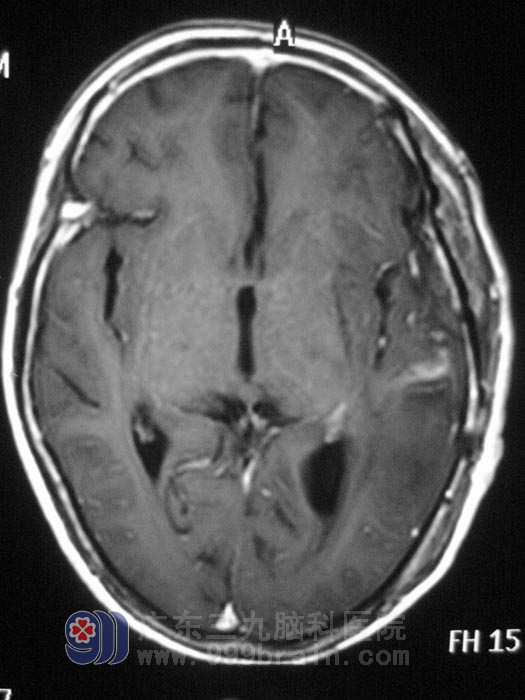

5月12日,由三九脑科医院神经外五科鲁明主任主刀,在全麻下行左颞叶占位性病变切除术,术中见灰色肿瘤,边界不清,质软,呈烂鱼肉样,在显微镜下予扩大切除,手术后给予抗炎、止血、神经营养等对症治疗,复查MR提示肿瘤全切,老人四肢活动正常,没有出现肢体偏瘫、失语等并发症。术后病理回报:(左颞叶)胶质母细胞瘤,WHOIV级。http://www.999brain.com/

手术后